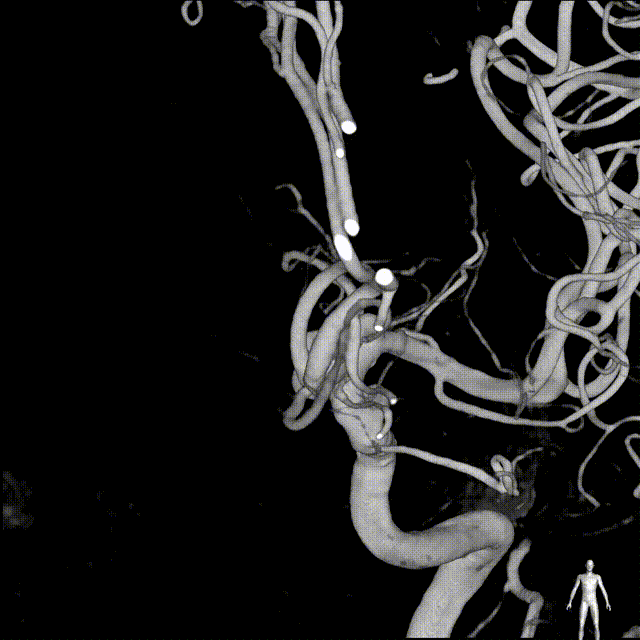

术中DSA造影:左侧颈内动脉3D造影,显示左侧颈内动脉海绵窦段动脉瘤,载瘤动脉远端直径3.36mm;近端直径4.20mm。

Headway™ 27 156cm微导管内输送FRED 4017血流导向密网支架,系统远端精准定位于预计着陆区远端(后交通动脉壶腹前端),确保扩口无效段跨过后交通动脉壶腹段。回撤微导管原位释放支架,释放过程支架头端无短缩,支架覆盖过动脉瘤颈后,手推造影确认前半段支架打开及贴壁情况良好。

完全释放FRED 4017血流导向密网支架,正、侧位及3D造影观察,载瘤动脉通畅、后交通动脉开放、支架贴壁良好、动脉瘤内造影剂滞留。